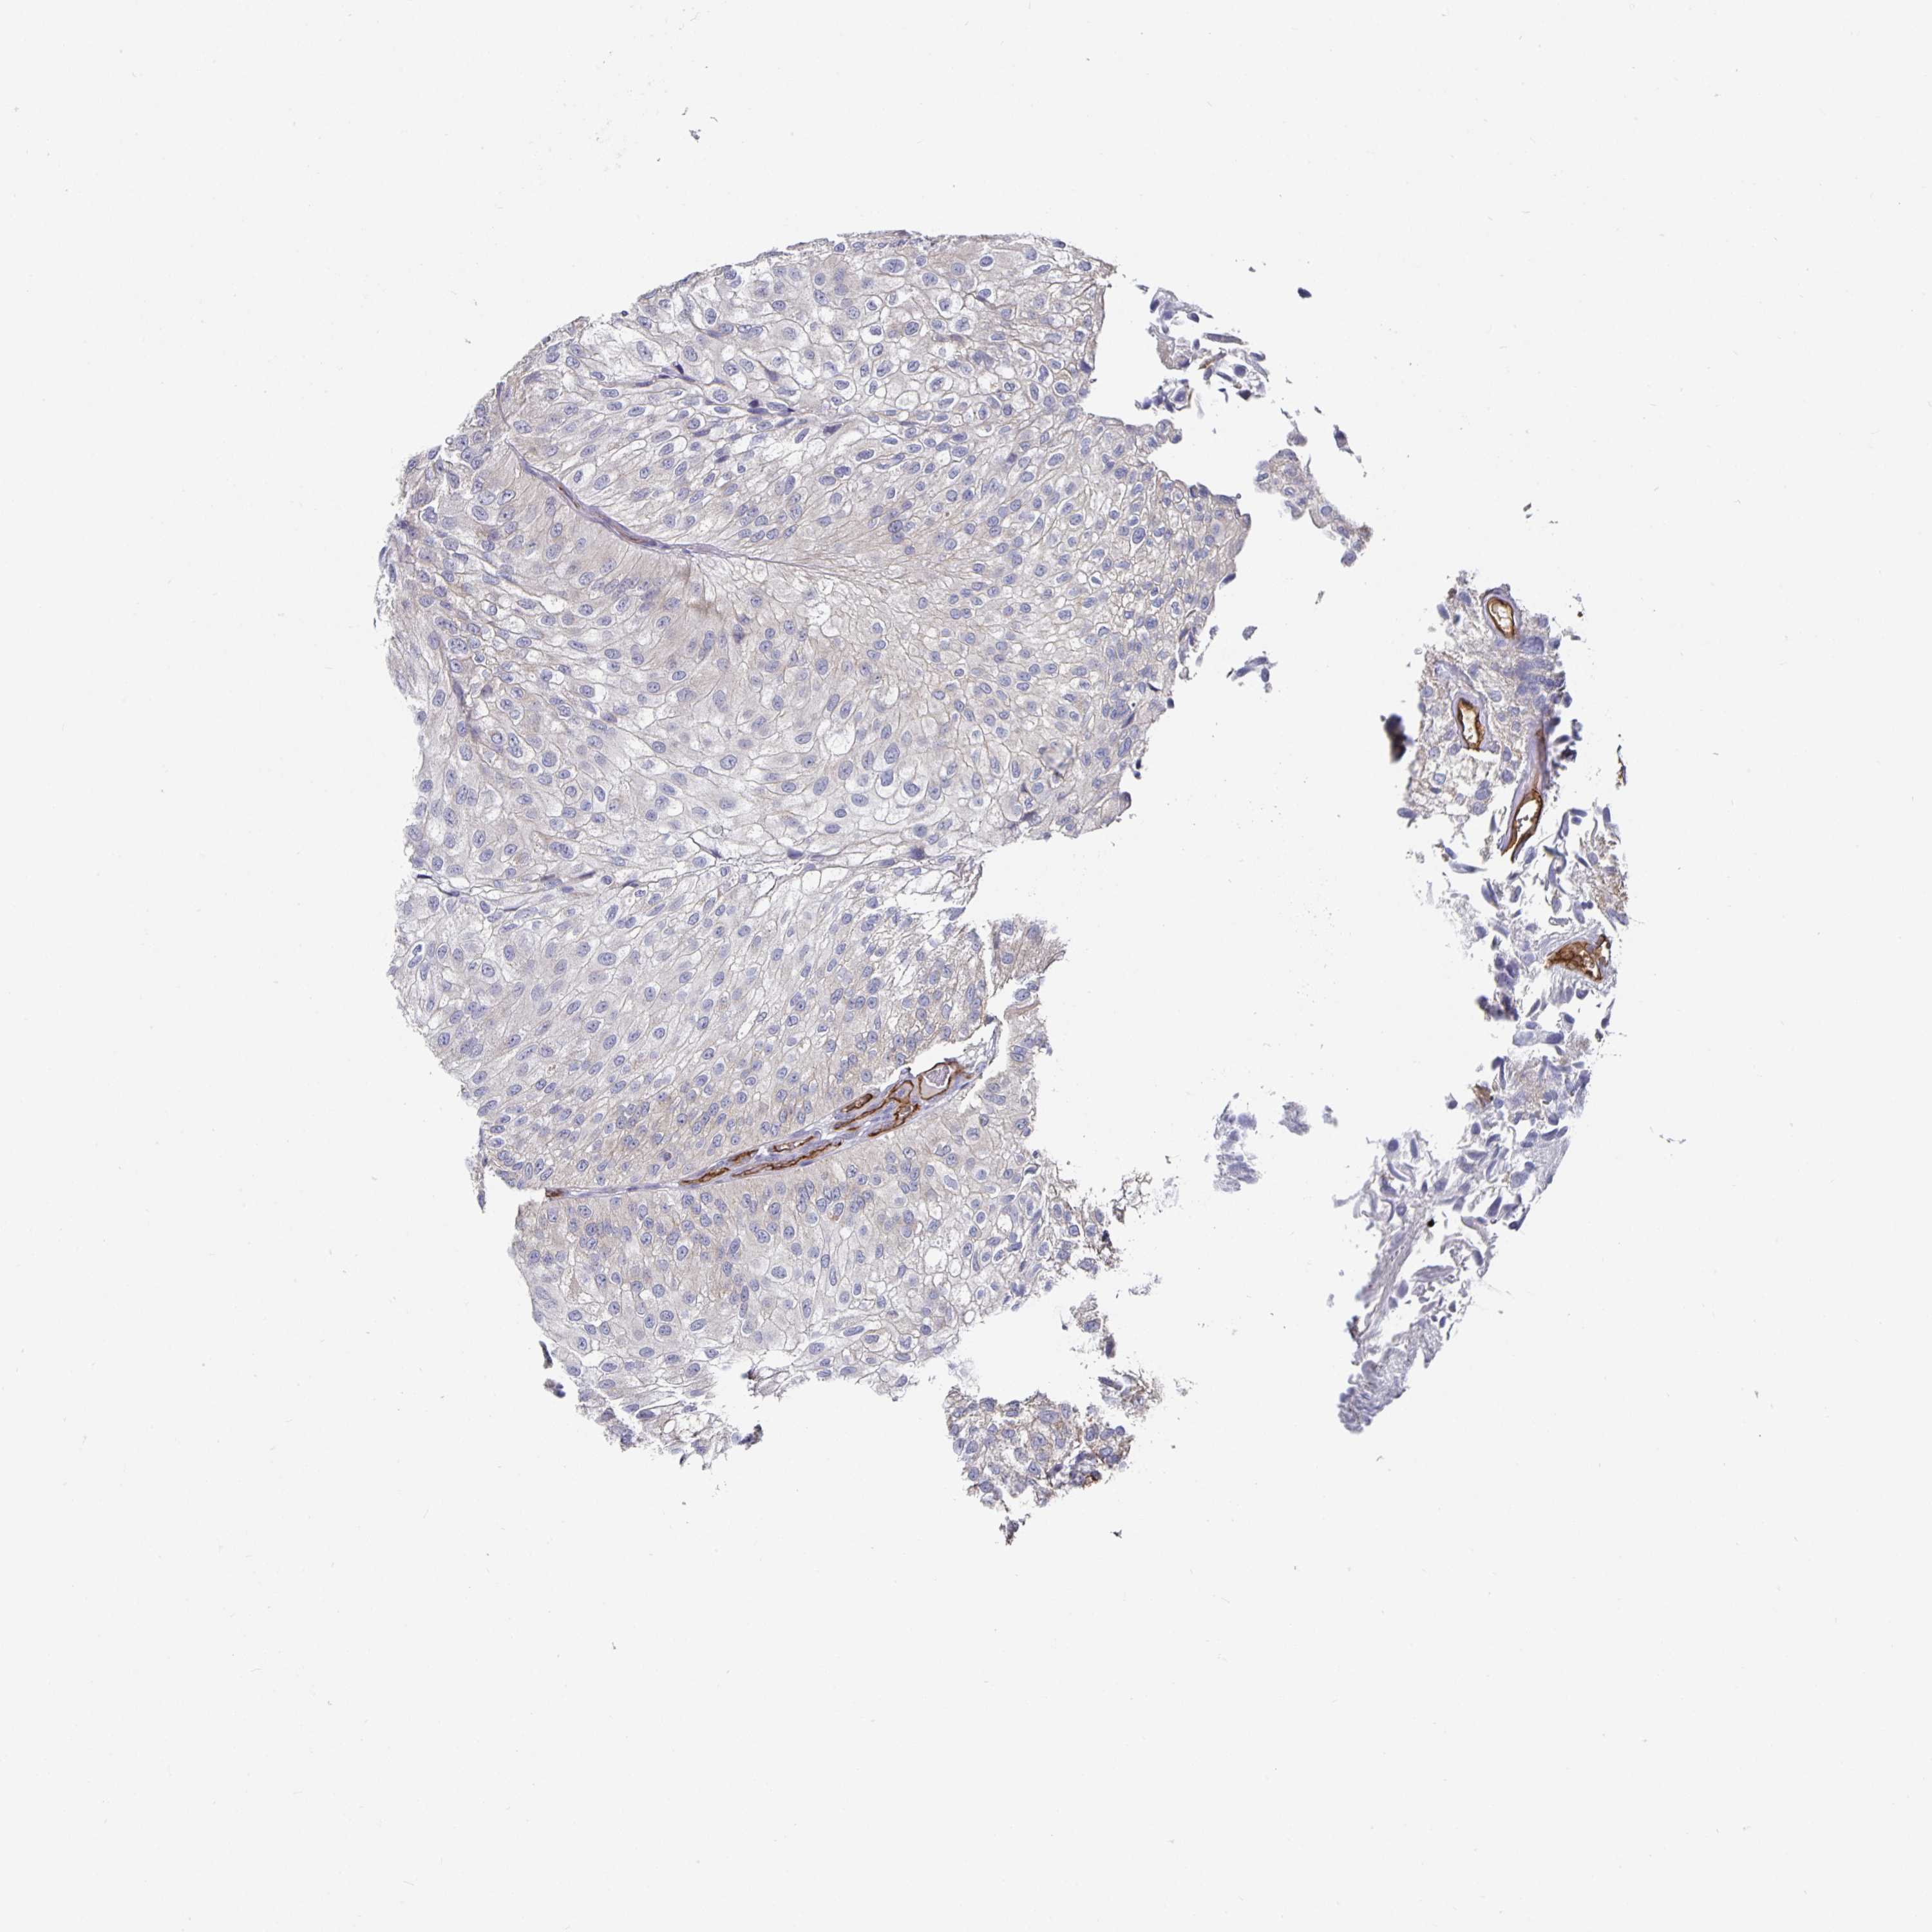

UROTHELIAL CANCER - Protein expressioni

A mouse-over function shows sample information and annotation data. Click on an image to view it in a full screen mode. Samples can be filtered based on level of antibody staining by selecting one or several of the following categories: high, medium, low and not detected. The assay and annotation is described here.

Note that samples used for immunohistochemistry by the Human Protein Atlas do not correspond to samples in the TCGA dataset.

Antibody stainingi

Antibody staining in the annotated cell types in the current human tissue is reported as not detected, low, medium, or high, based on conventional immunohistochemistry profiling in selected tissues. This score is based on the combination of the staining intensity and fraction of stained cells.

Each image is clickable and will lead to virtual microscopy that enables deeper exploration of all samples and also displays staining intensity scores, fraction scores and subcellular localization as well as patient and tissue information for each sample.

HPA002110

HPA045507

CAB016169

CAB062558

CAB068219

CAB068220

Urothelial carcinoma, High grade

Urothelial carcinoma, NOS

Urothelial carcinoma, Low grade